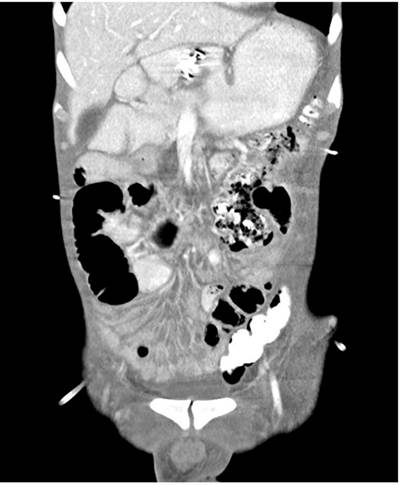

Surgical time was scheduled for a gastric bypass surgery where gastrojejunostomy was performed using conventional technique. On the fifth postoperative day, he presented clinical deterioration due to febrile episodes, abdominal pain, and tachycardia. A new abdominal tomography was performed, reporting an intra-abdominal collection of pus on the left flank of 12 x 12 x 5 cm secondary to the jejunal fistula process. Hence, percutaneous drainage management of the collection was performed by interventional radiology and drainage catheter placement. In addition, an EGD was performed to conduct a pyloric exclusion technique with an Ovesco (over-the-scope-clip) device for managing the jejunal fistula, which was technically successful.

Se realizó el manejo de la colección con drenaje percutáneo por radiología intervencionista y alojamiento de catéteres de drenaje en el que se obtuvo 150 mL de contenido purulento e intestinal, con lo que se logró controlar el proceso infeccioso y optimizar la condición clínica del paciente. 3 días después del drenaje percutáneo, teniendo en cuenta los hallazgos intraoperatorios y la gastroyeyunoanastomisis laterolateral, se decidió realizar manejo endoscópico de la fístula yeyunal proximal por medio de exclusión pilórica, para disminuir el flujo del contenido intraluminal por el asa comprometida, concomitantemente con manejo farmacológico multimodal con inhibidor de bomba de protones (IBP), opioide, antidiarreico y nutrición parenteral. Dadas las comorbilidades del paciente y en busca del procedimiento menos invasivo, se decidió realizar dicha exclusión pilórica con el dispositivo Ovesco, teniendo en cuenta la adecuada funcionalidad de la gastroyeyunoanastomosis, con la que se obtuvo éxito técnico (Figura 3).

Al quinto día posterior al procedimiento endoscópico se realizó como seguimiento imagenológico una radiografía de vías digestivas que confirmó la no continuidad pilórica con adecuada permeabilidad de la gastroyeyunoanastomosis y tomografía abdominal contrastada que mostró una disminución de la colección intraabdominal sin extravasación del medio de contraste (Figuras 4 y 5).

Se exploró el estómago hasta el píloro y se evidenció un abundante lago gástrico, gastroyeyunoanastomosis permeable sobre la pared anterior, se identificó el píloro y por técnica de succión se realizó afrontamiento de los bordes del píloro con clip Ovesco 12/6 GC. En la revisión se observó un ángulo permeable, por lo que se colocó el segundo clip Ovesco 12/6 GC ocluyendo el píloro en su totalidad como parte de la exclusión pilórica indicada.